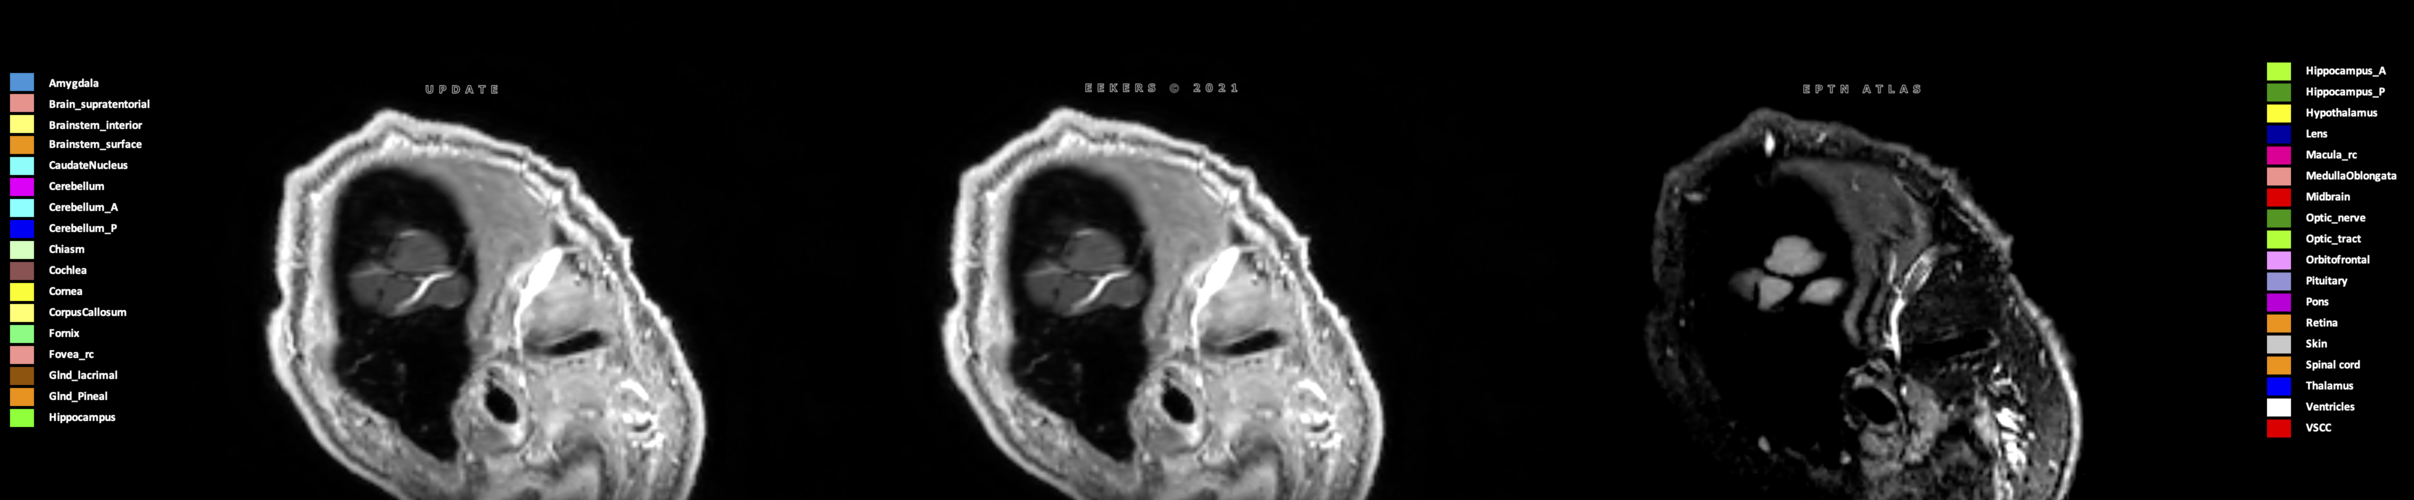

Eekers et al. have published an international neurological atlas for contouring of organs at risk in consensus with the European Particle Therapy Network (EPTN) in 2018 and an update in 2021. The purpose of this consensus atlas is to decrease inter- and intra-observer variability in delineating OARs relevant for neuro-oncology.

Three-dimensional delineation of the 25 consensus OARs for neuro-oncology are shown on CT (WW/WL 120/40, 3000/600), 3T MR images, (T1Gd, T2FLAIR 1mm) and 7T MR (MP2RAGE 0.7 mm). All are presented in transversal, sagittal and coronal view.

Eekers D, Di Perri D, Roelofs E, Postma A, Troost EG. EPTN International Neurological Contouring Atlas - 2021 Update CancerData, 2021. doi:10.17195/candat.2021.02.1